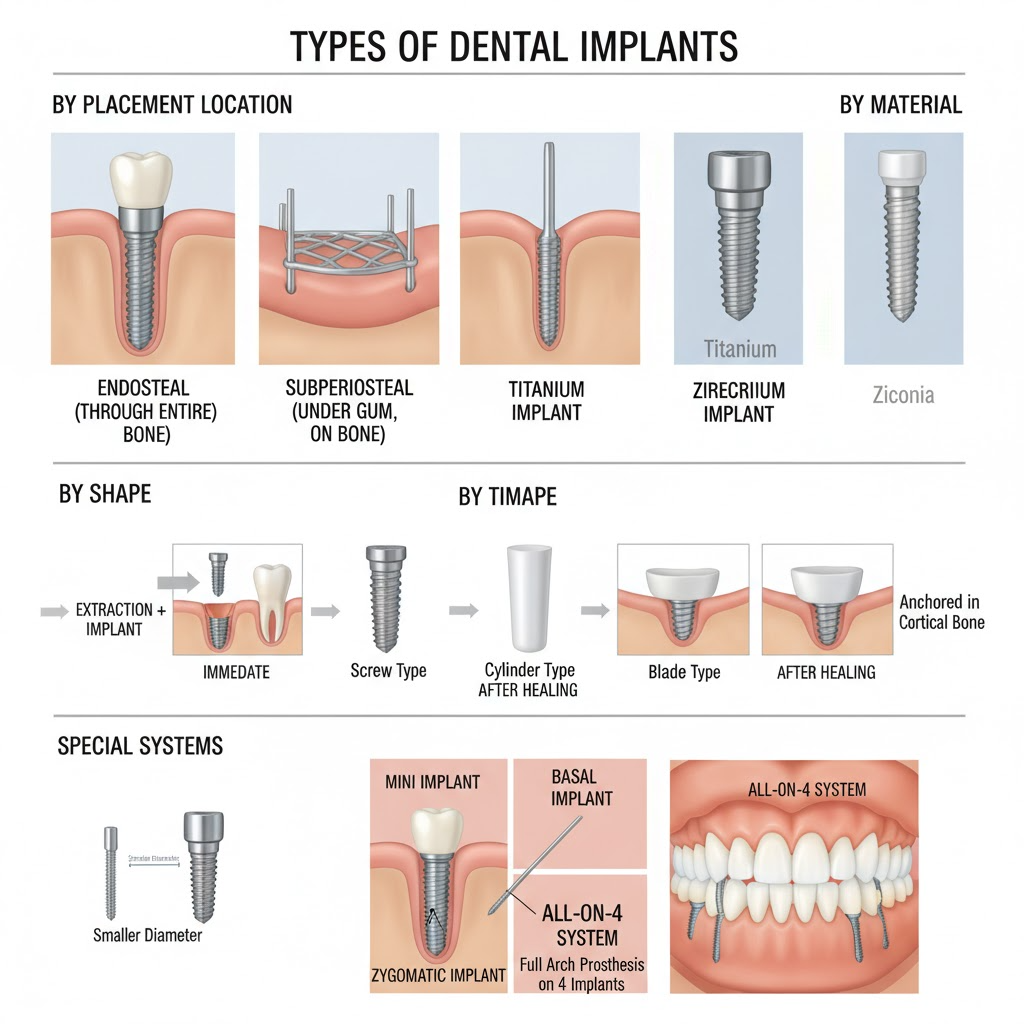

Diş İmplantları, eksik diş köklerini değiştirmek için cerrahi olarak çene kemiğine yerleştirilen devrimci titanyum direklerdir, değiştirme dişleri için kalıcı, kararlı bir temel sağlar. Geleneksel protez veya köprülerden farklı olarak, diş implantları osseointegrasyon adı verilen bir süreçle çene kemiğinizle doğrudan entegre olur, doğal diş köklerini taklit eden bir bağ oluşturur. Çoklu diş eksikliklerinde All-on-4 veya All-on-6 gibi gelişmiş teknikler kullanılabilir. Bu entegrasyon olağanüstü kararlılık sağlar ve eksik dişlerle tipik olarak oluşan kemik kaybını önler. Diş implantları diş değiştirme için altın standart olarak kabul edilir çünkü doğal diş gibi görünür, hissedilir ve işlev görür. Çıkarılabilir cihazlara olan ihtiyacı ortadan kaldırır, üstün çiğneme işlevi sağlar ve yüz yapısını korur. Modern diş implantları deneyimli implantologlar tarafından yapıldığında %95'i aşan başarı oranlarına sahiptir, onları mevcut en güvenilir diş prosedürlerinden biri yapar. Tek dişleri, çoklu dişleri değiştirebilir veya tam protezleri destekleyebilir, çeşitli diş kaybı durumları için çok yönlü çözümler sunar.

Deneyimli implantologlarımız başarılı implant yerleştirme ve optimal uzun vadeli sonuçlar sağlamak için en son teknikleri ve premium malzemeleri kullanan yüksek eğitimli uzmanlardır. Straumann, Nobel Biocare ve diğer önde gelen markalar dahil olmak üzere son teknoloji implant sistemlerini kullanırız, farklı hasta ihtiyaçları, bütçeleri ve anatomik gereksinimleri karşılamak için çeşitli seçenekler sunarız. Gelişmiş teknolojimiz hassas implant yerleştirme için 3D görüntüleme, bilgisayar destekli cerrahi ve dijital tedavi planlaması içerir. Çene kemiğinizle biyouyumlu olan ve doğal olarak entegre olan sadece yüksek kaliteli titanyum implantlar kullanırız. İmplantologlarımız kemik grefti, sinüs kaldırma ve tam ağız rehabilitasyonu dahil karmaşık vakalarda kapsamlı eğitime sahiptir. Ayrıca uygun olduğunda implant yerleştirme ile aynı gün geçici dişler almanıza olanak tanıyan anında yükleme implantları da sunuyoruz. Kapsamlı yaklaşımımız kapsamlı cerrahi öncesi planlama, gelişmiş cerrahi teknikler ve titiz cerrahi sonrası bakım içerir.